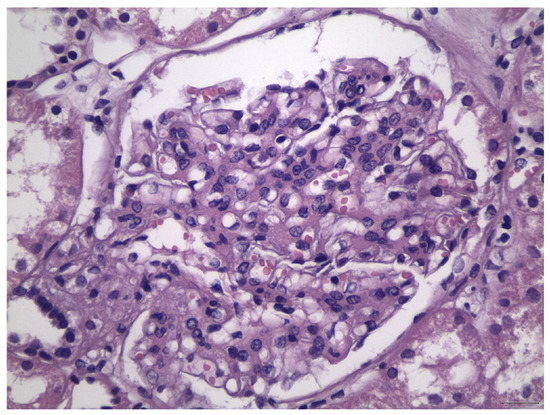

- Haas, M. Histologic subclassification of IgA nephropathy: A clinicopathologic study of 244 cases. Am. J. Kidney Dis. 1997, 29, 829–842. [Google Scholar] [CrossRef]

- Cattran, D.C.; Coppo, R.; Cook, H.T.; Feehally, J.; Roberts, I.S.D.; Troyanov, S.; Alpers, C.E.; Amore, A.; Barratt, J.; Berthoux, F.; et al. The Oxford classification of IgA nephropathy: Rationale, clinicopathological correlations, and classification. Kidney Int. 2009, 76, 534–545. [Google Scholar] [CrossRef] [PubMed]

- Roberts, I.S.D.; Cook, H.T.; Troyanov, S.; Alpers, C.E.; Amore, A.; Barratt, J.; Berthoux, F.; Bonsib, S.; Bruijn, J.A.; Cattran, D.C.; et al. The Oxford classification of IgA nephropathy: Pathology definitions, correlations, and reproducibility. Kidney Int. 2009, 76, 546–556. [Google Scholar] [CrossRef] [PubMed]

- Jennette, J.C.; Olson, J.L.; Silva, F.G.; D’Agati, V.D. Heptinstall’ s Pathology of the Kidney, 7th ed.; LWW: Philadelphia, PA, USA, 2015. [Google Scholar]